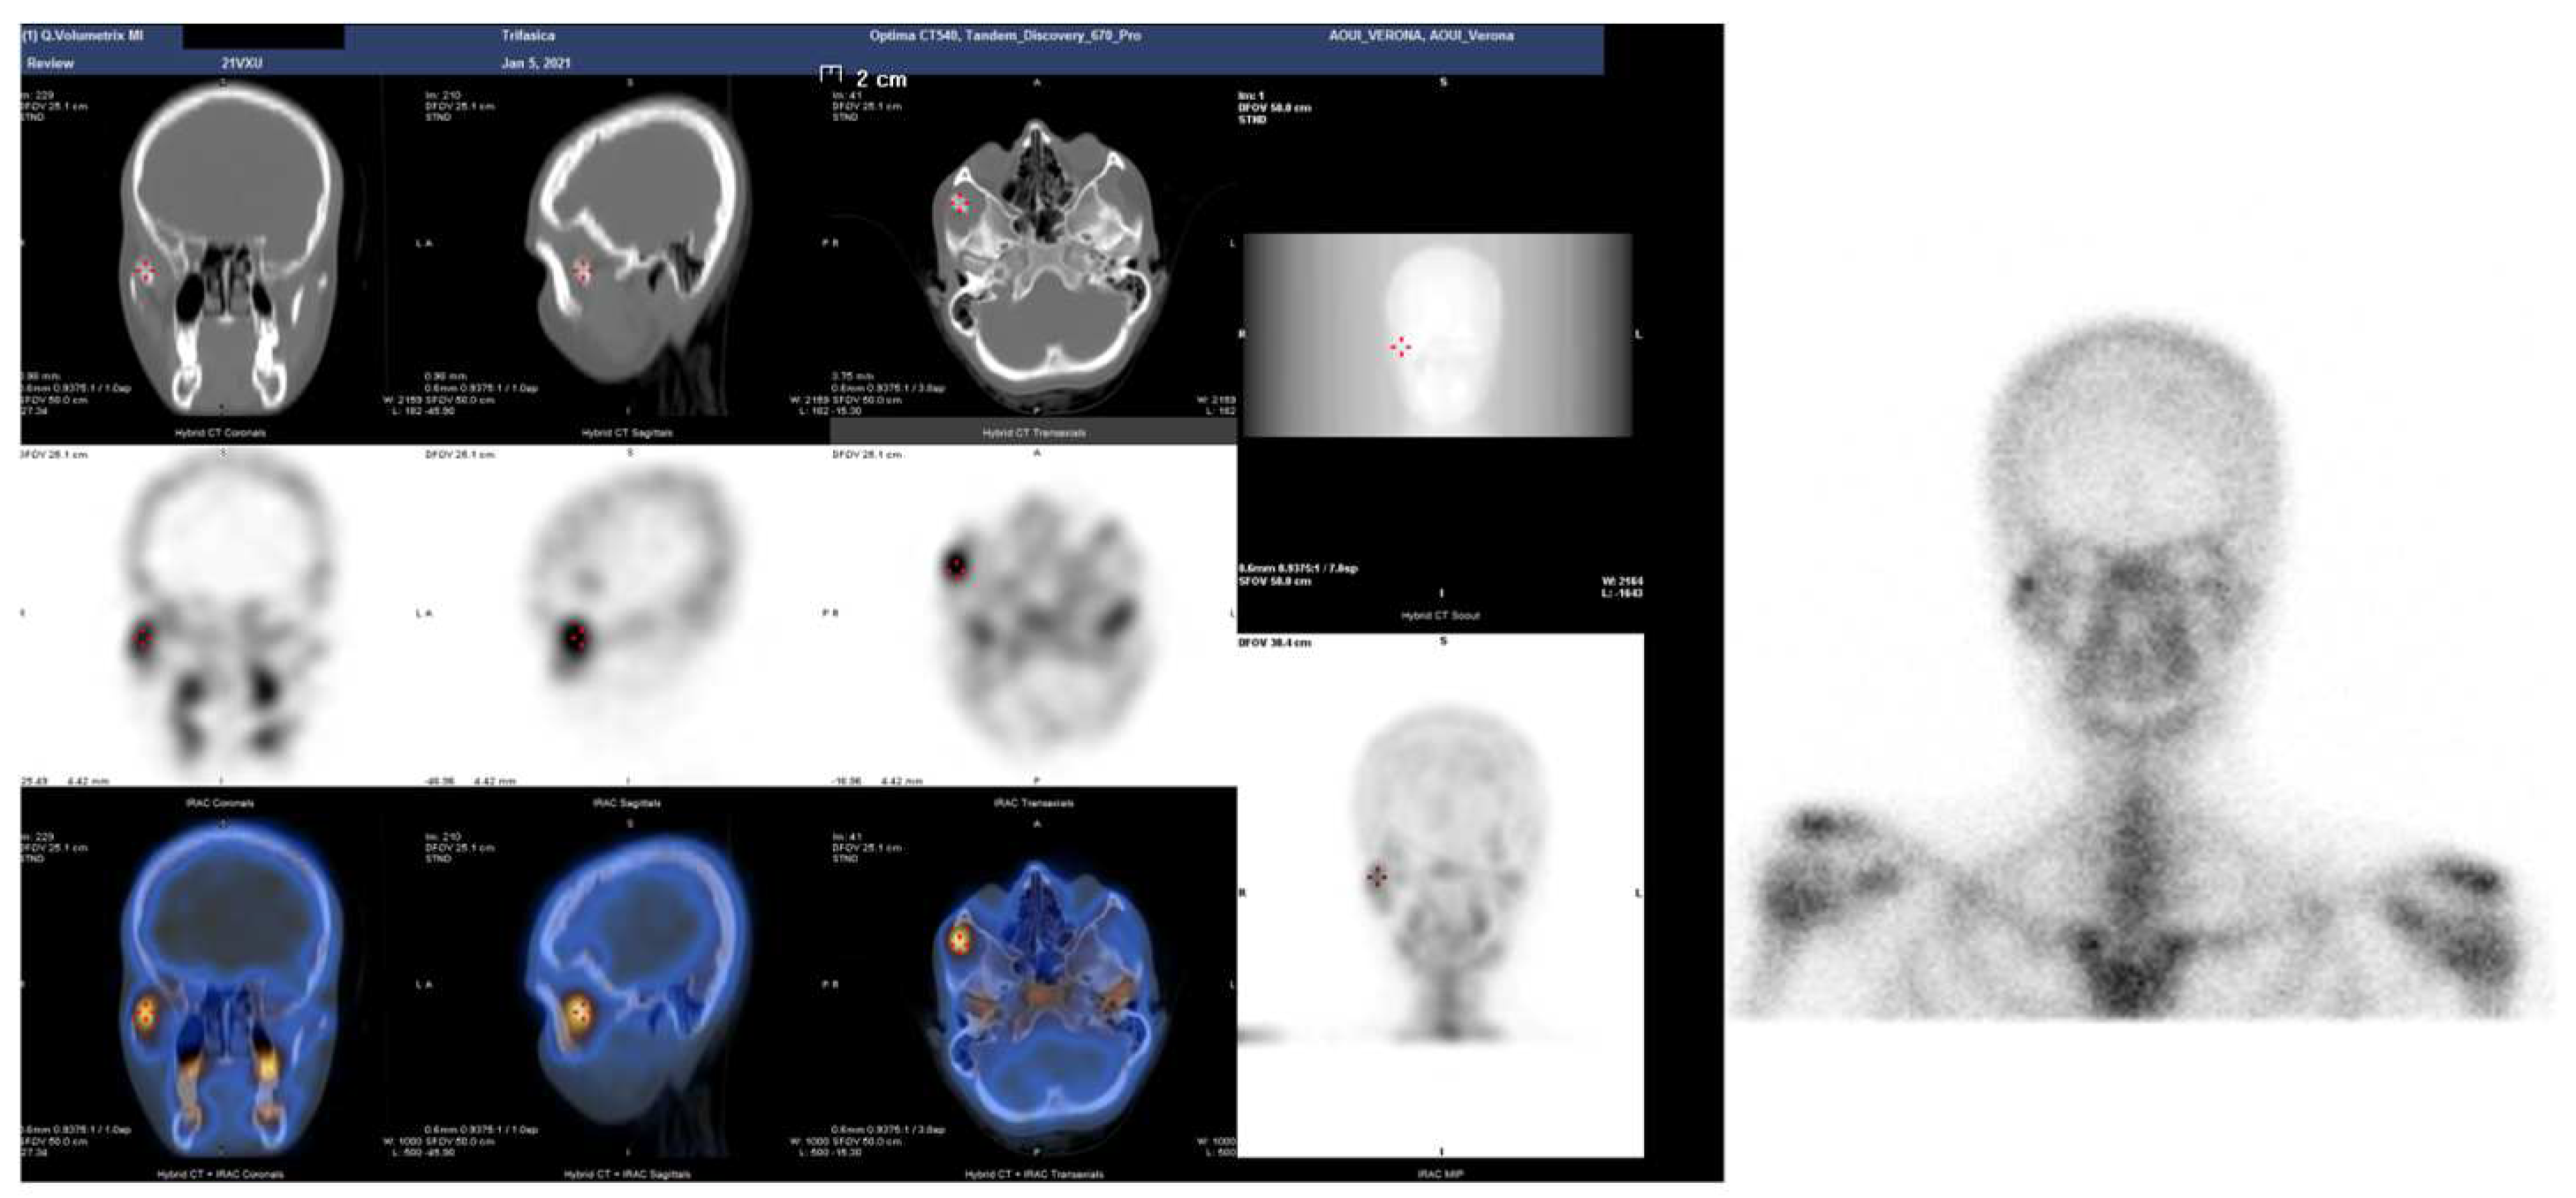

| 114 | Raccampo et al. | 2022 | 19 | F | R | CCE | 25 | 40 | Intraoral coronoidectomy | 12 | No |

| 115 | Raccampo et al. | 2022 | 18 | M | R | OC | 20 | 44 | Intraoral coronoidectomy | 12 | No |

| 116 | Raccampo et al. | 2022 | 23 | M | R/L | CH | 20 | 37 | Intraoral coronoidectomy | 14 | No |